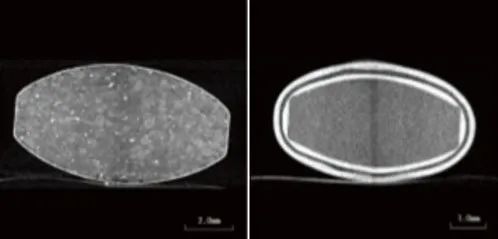

圖4片劑A的CT效果圖(左)圖5片劑B的CT效果圖(右)

在本例中,觀察到兩種具有不同結(jié)構(gòu)的片劑(片劑A和B)(圖2)。片劑的透視圖像如圖3所示。

分析片劑圖像的一個例子除了觀察片劑內(nèi)部外,CT X射線圖像還可用于執(zhí)行各種圖像分析。在本例中,利用CT數(shù)據(jù)結(jié)合三維圖像處理軟件,分析藥物的分布狀態(tài),分析藥物的層厚。